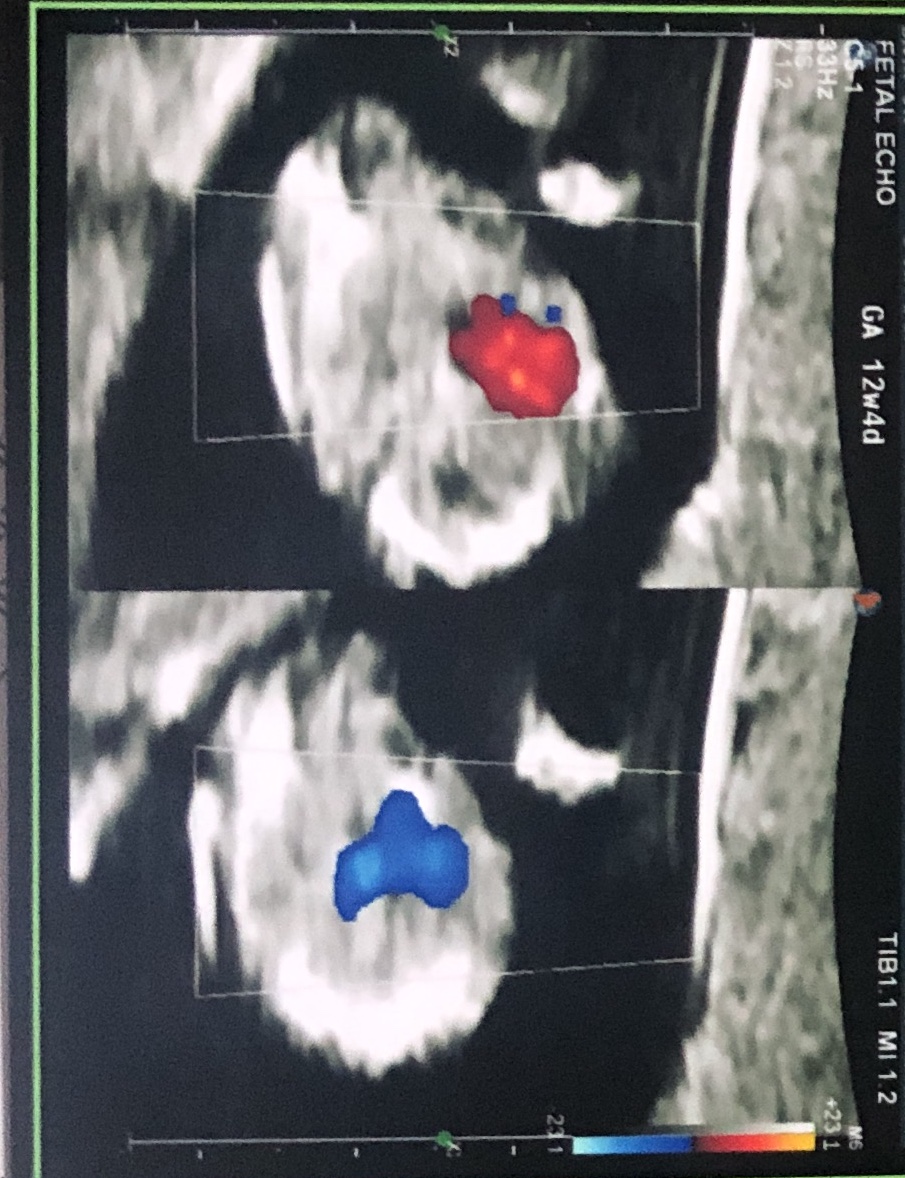

Little anxious to find our little one’s gender. Attached are ultrasound images at 12+4 days (age as per CRL dating)Attachment 42397Attachment 42398Attachment 42397Attachment 42398